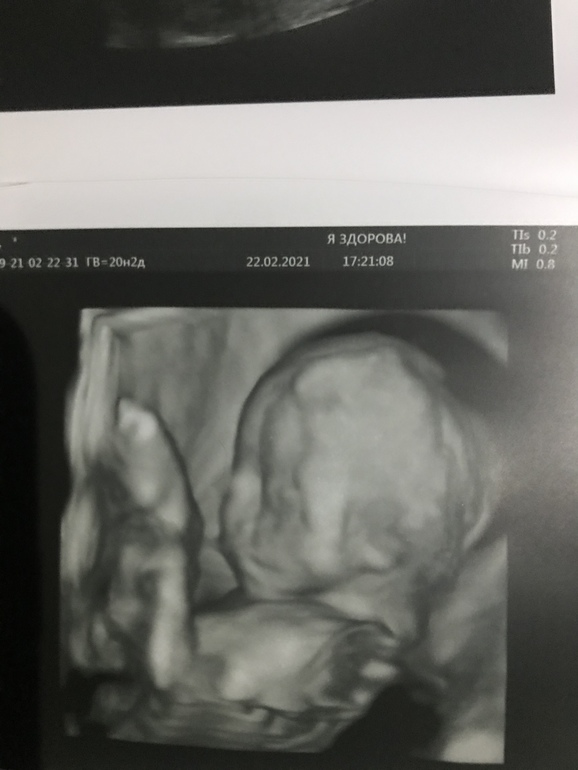

Сыночек +- на 384 грамма, идёт по сроку с небольшим опережением. В сердечке нашли хорду один в один таких же размеров и такого же расположения, как была у Аарона. Не критично, да и надеюсь что как и в случае со старшеньким, рассосётся к родам. На всех фотографиях тоже видно сходство с братом уже сейчас: выпяченная вперёд верхняя губа выдаёт))

Вот он, малышочек: